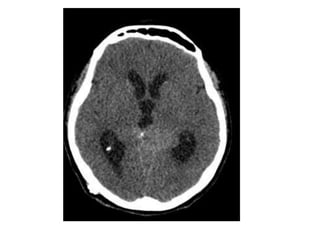

Axial nonenhanced CT shows a large pineal region mass with resultant hydrocephalus ,

the pineal calcifications are exploded toward the periphery (arrows)